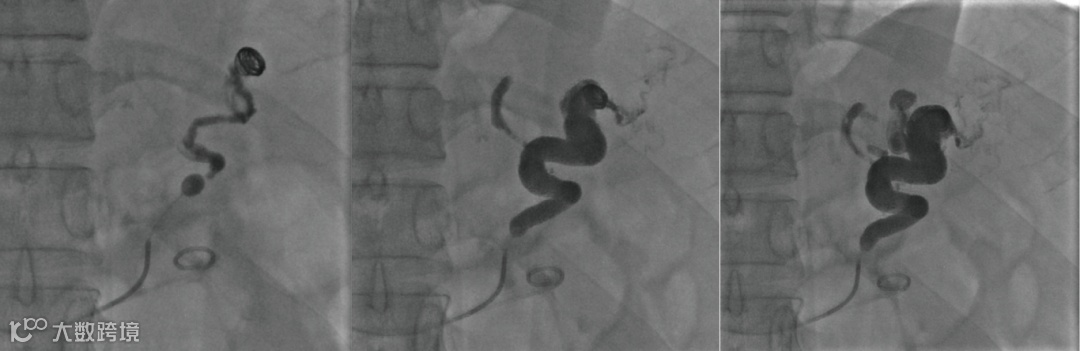

建立门体静脉分流道后行门静脉、脾静脉造影

胃冠状静脉造影

超选择插入至曲张静脉,注入弹簧圈栓塞至血流明显减缓

超选择插入至曲张静脉,注入弹簧圈栓塞,后经微导管注入聚桂醇至曲张静脉血流基本停滞

后续手术,其它器械操作:分流道成形

术后造影(即刻效果):胃底曲张静脉血管网未见显影